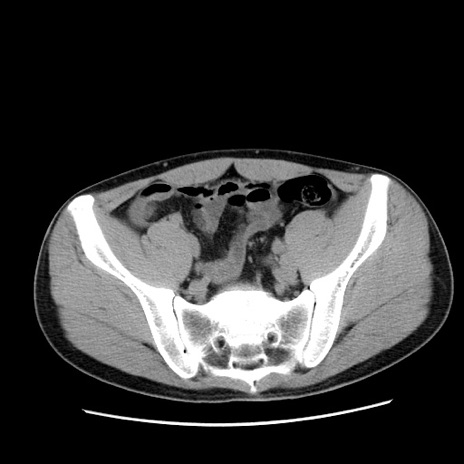

症例36(横断像)

【症例】20歳代 男性

【主訴】心窩部痛

【現病歴】今朝より上腹部痛あり。一旦軽快していたが再度出現したため救急要請。昨日夕に白身の魚を含む刺身を食べた。

【身体所見】BP 136/89mmHg、HR 74/min、BT 37.0℃、腹部:膨満、軟、心窩部に圧痛あり。反跳痛なし、筋性防御なし、腸雑音やや亢進あり。

【データ】WBC 17700、CRP 0.48